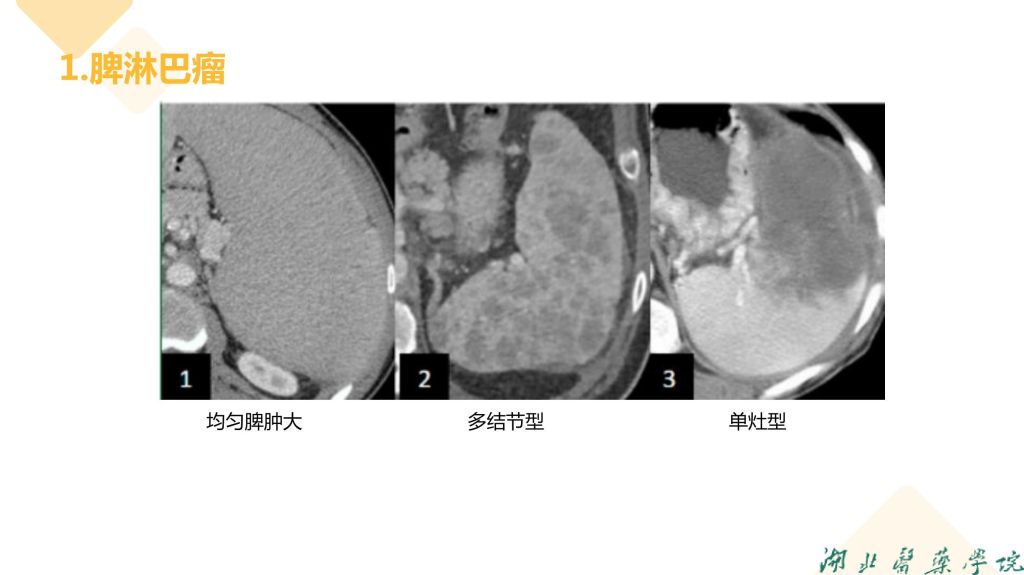

病例分享-脾脏实质性占位性病变

杨雪君 7790必发集团

病例分析-脾脏实性占位性病变-杨雪君.pdf